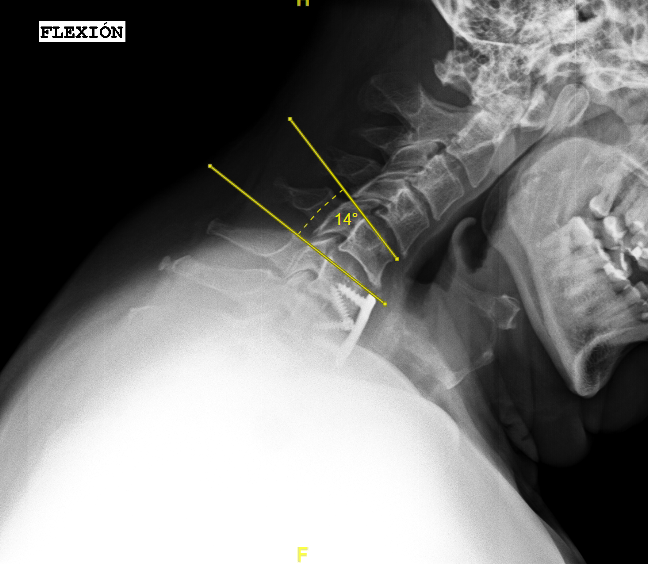

Las RX dinámicas reflejan la ausencia de fusión C6-C7